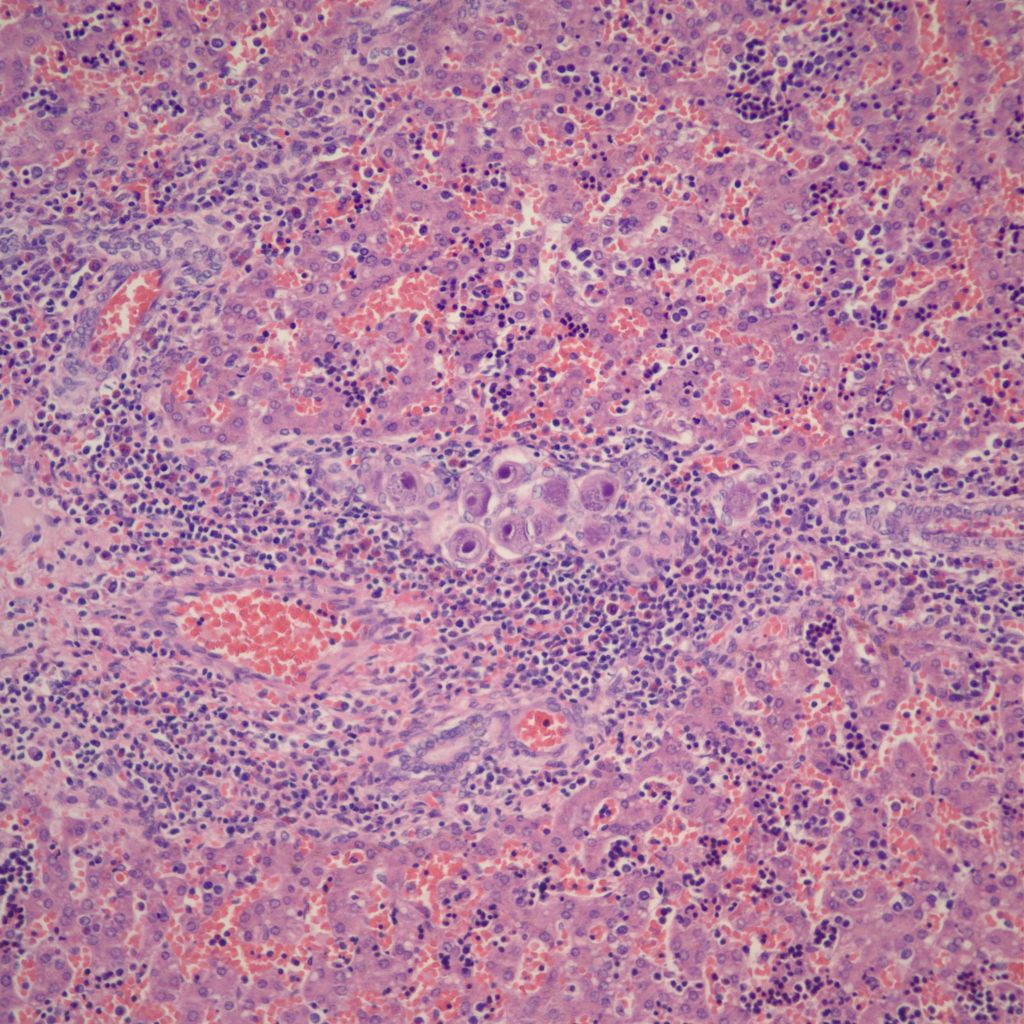

Hematopoiesis: The liver is a major site of fetal hematopoiesis. Erythropoiesis and megakaryocytopoiesis occur in the liver sinusoids. Erythropoiesis is increased with conditions requiring increased production such as fetal hemolysis or hemorrhage, and in macrosomic infants of diabetic mothers2. The extent of erythropoiesis decreases with gestational age (Fig 4a, b).

With pathologically increased erythropoiesis there is often grouping of cells at the same stage in erythropoietic development (fig 5a, b).